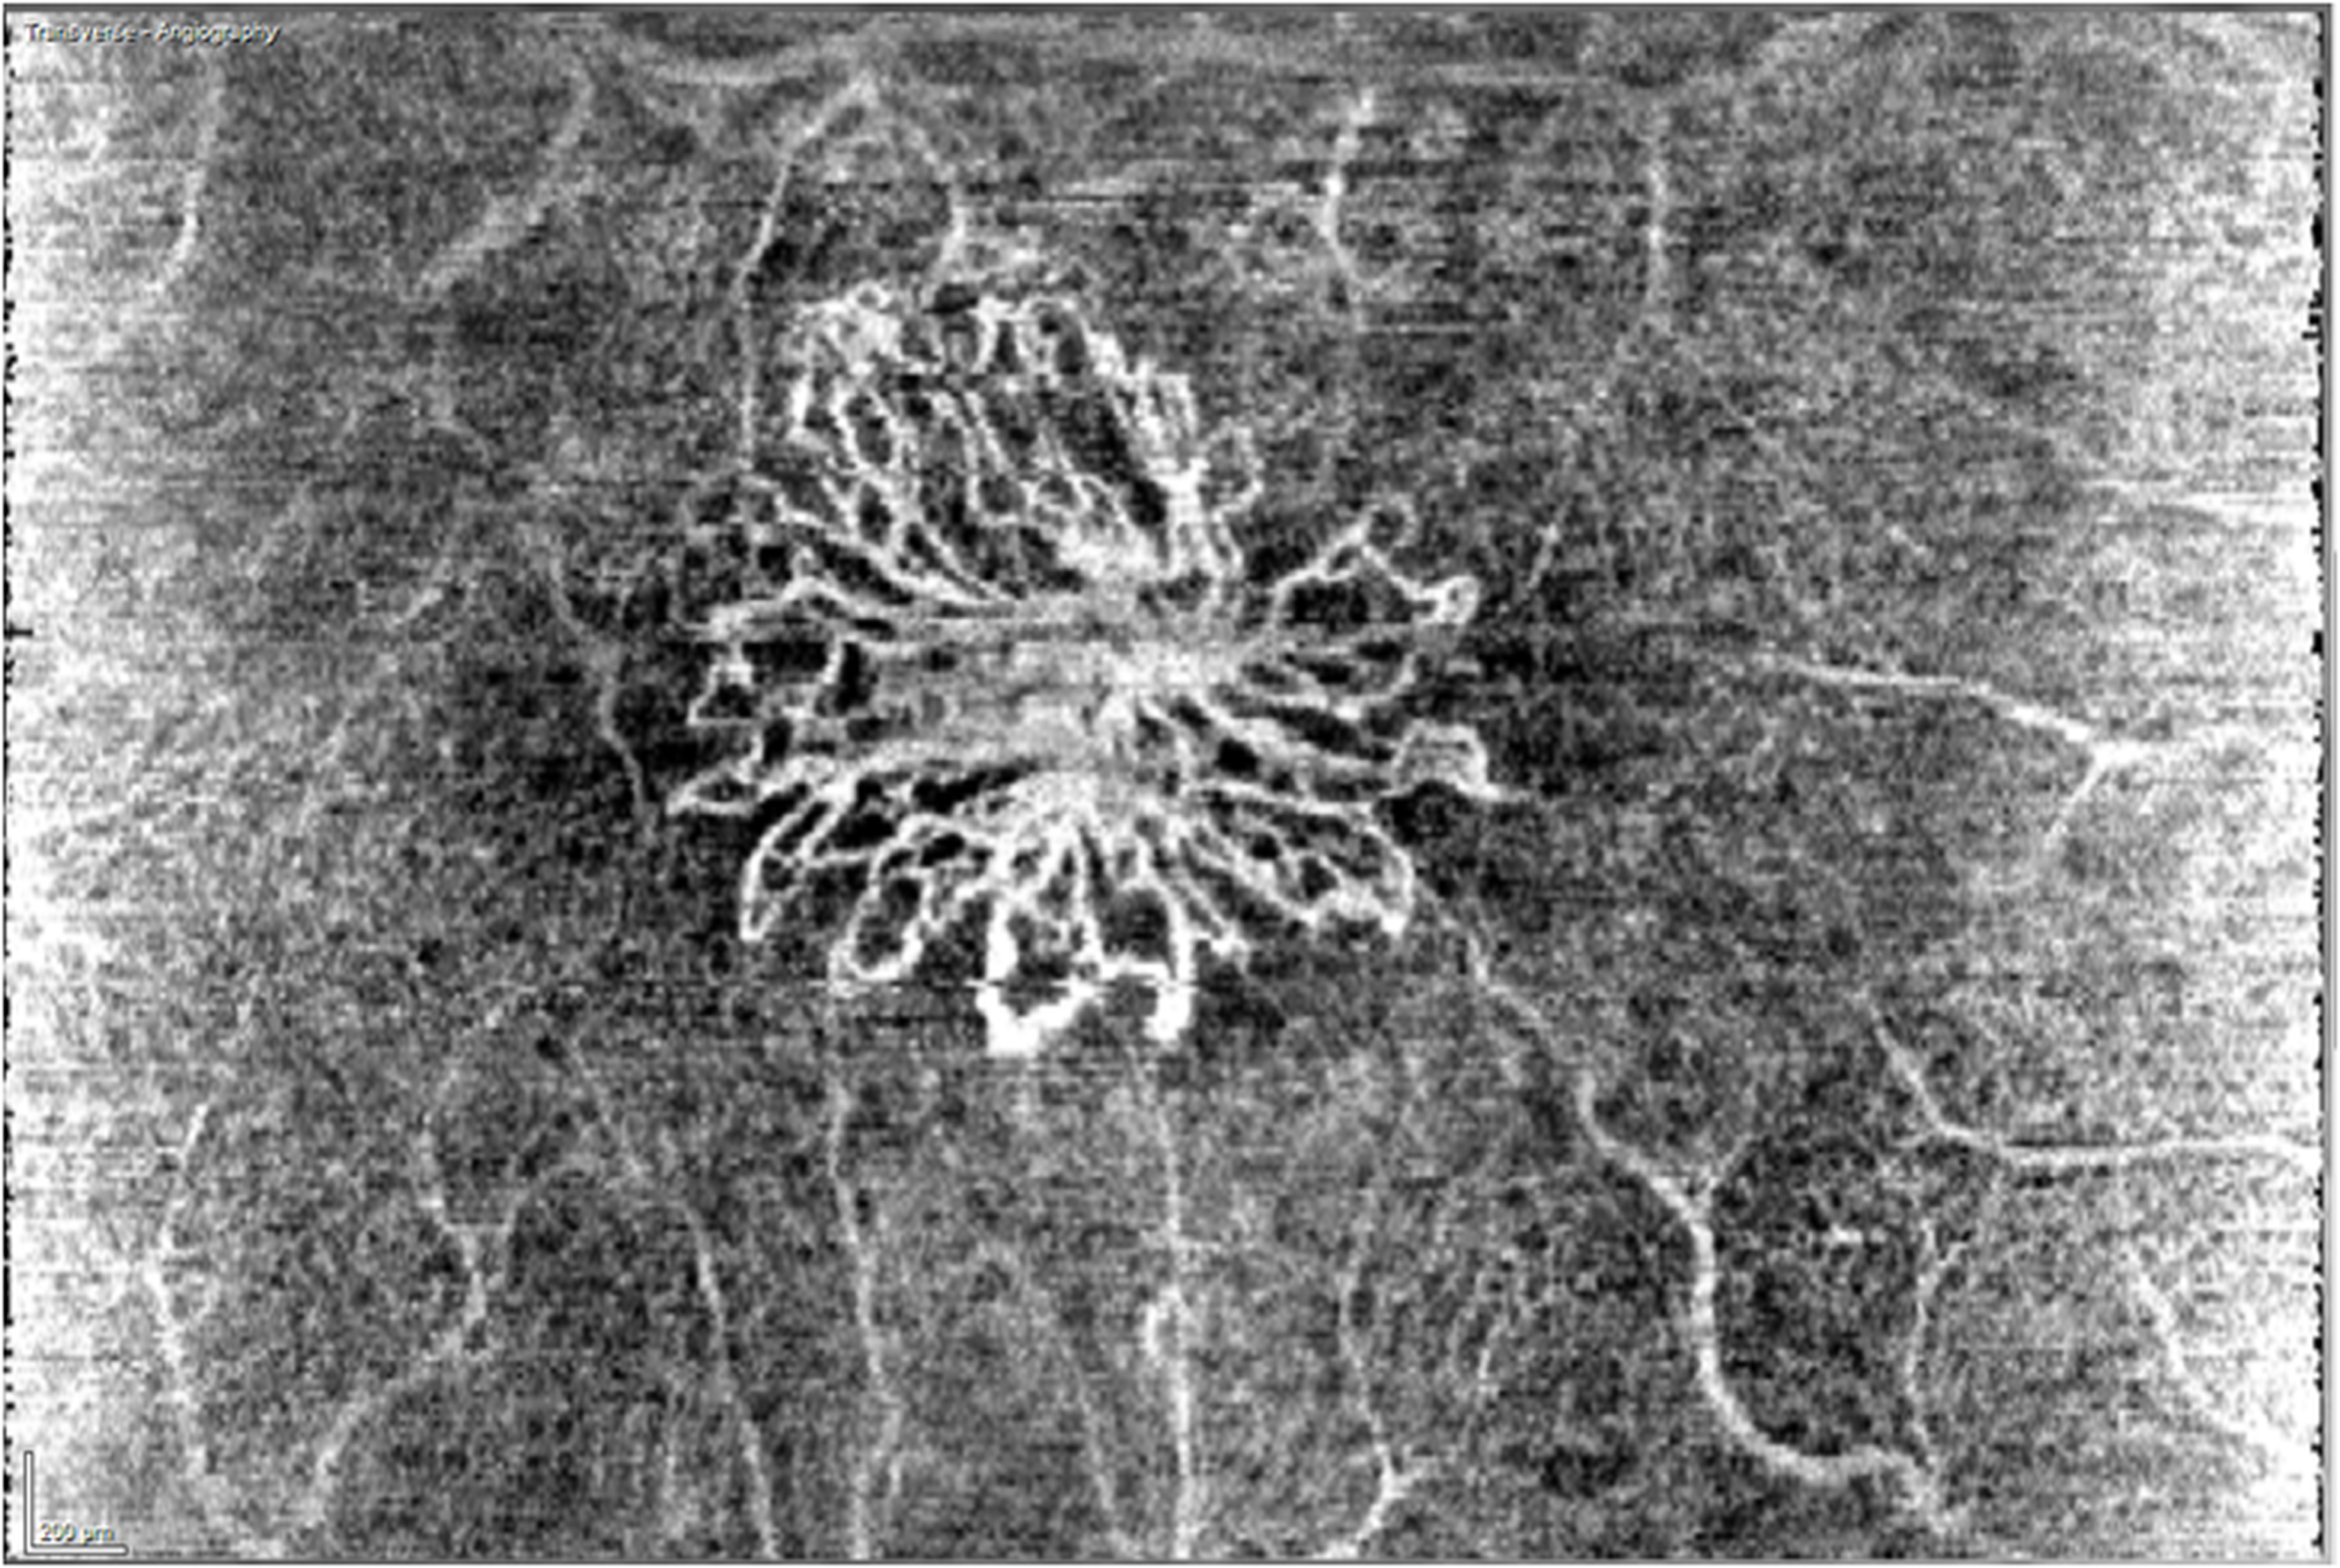

Il Centro Oculistico Bresciano è tra i primissimi centri in Lombardia a dotarsi della nuova tecnologia Angio OCT, ossia la possibilità di eseguire scansioni vascolari retiniche senza la necessità di mezzo di contrasto (colorante fluorescina o indocianina) endovenoso. Tale tecnologia genera un imaging della retina centrale sfruttando il movimento dei globuli rossi all’interno dei capillari retinici in modo rapido e non invasivo.

Gli ultimi lavori pubblicati nella letteratura scientifica concordano nel sostenere che sin da ora l’Angiografia con OCT, grazie alla rilevazione dell’area di neovascolarizzazione, sia la metodica migliore e meno invasiva, nella valutazione delle maculopatie neovascolari e nella scelta dell’approccio terapeutico.